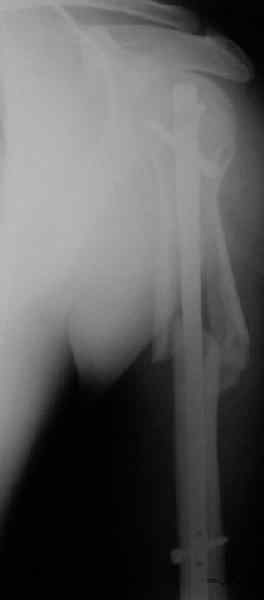

Дорогие коллеги,Мужчина 44 л. упал с крыши дачи 6 августа. Картинки в приложении. Лет 5 назад нде-то оперирован по поводу привычного вывихв этого же плеча.После операции не вывихивал до этой травмы.Как тут лечить? Есть ли шансы на закрытое вправление? Чем лучше фиксировать? Какие меры принять с учетом бывшего и нынешнего вывиха? Заранее спасибо. Dear colleagues, A male 44 y.o. admitted to our unit. Injured at Aug. 6 - fall from 3 m. Images attached. Five years ago was operated somewhere else for recurrent dislocation of thу same shoulder, no data what was done. What would be optimal treatment option? Any chance of closed reduction? What should be done to address the current and past dislocations? THX.

This is an anterior fracture/dislocation with shaft extension-no chance for closed reduction-probably contraindicated, especially since the injury is now 19 days old. We do these supine on a radiolucent table with an arm board extension-you now have an unobstructed radiographic view of the entire upper extremity both AP and lateral with excellent axillary views of the glenohumeral joint to assess your reduction and screw placement. This is the perfect indication for a locking plate via the traditional deltopectoral approach. Use the biceps tendon to stay anatomically oriented during the approach and be sure to check the rotation post plate application. In general, we have not performed any soft tissue stabilization procedures during the fixation, may stay away from external rotation past neutral during rehab and early motion protocol. This one should do fine.

Попытка закрыто изменить положение не удалась. Передним доступом сделали открытую репозицию, гленоид без особенностей. Временно фиксировали спицами и остроконечным костедержателем. Фиксировали гвоздем T2 PHN (Stryker). Для профилактики вывихов после введения проксимальных винтов ротировали дистальный отдел кнаружи на 30

градусов как аналог остеотомии по Weber. Снимки в приложении. Комментарии и критика привествуются.

Attempt of closed reduction failed. Open reduction via anterior approach. The head was temporarily fixed by wires and sharp clamps. Fixation by a nail - T2 PHN (Stryker). The distal fragment has been rotated 30 degrees externally after proximal locking for dislocation prevention as "virtual" Weber osteotomy. Images attached.